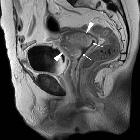

Giant

fibroepithelial polyp of the uterine cervix. Sagittal (i) and fat-suppressed coronal (j) T1-weighted images after intravenous gadolinium showed heterogeneously enhancing cervical mass (arrowheads), normal mucosal enhancement at the vagina (thin arrows).